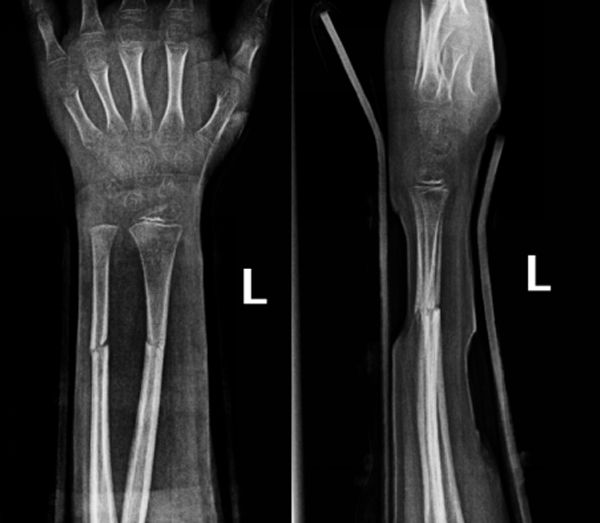

县人民医院骨科团队对其伤情进行全面评估后,与其家属共同选择了“放弃手术”,以采用手法复位闭合治疗加外固定术为患儿采取保守治疗。医护团队在C臂透视机引导下,凭借丰富经验与娴熟技巧,精准完成骨折端的对位对线,并实施夹板外固定,影像显示,骨折对位对线良好,达到功能复位标准。

术中复位透视